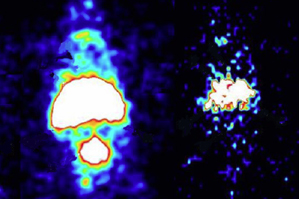

A few decades ago, Khaw figured out a way to diagnose various forms of heart cell damage — the damage could be from heart attack, a cardiac autoimmune defect, a heart transplant rejection, it didn’t matter. If the cells were damaged, Khaw could find them.

When a heart cell gets hurt, the outer membrane ruptures, exposing the contractile units of the cells just beneath it. Khaw figured that if he tagged imaging molecules (which glow at damaged sites) to antibodies that seek out those contractile mechinary in the muscle cells, then he could find places where they were exposed and by extension, places where the heart tissue has been damaged.

The current technology allows doctors to see tumors when they have mass of greater than 1 or 2 grams. “But you want to be able to see milligram amounts,” said Khaw. “You want to see it before it’s large enough so it can send out metastatic lesions.” And this is exactly what he accomplished.